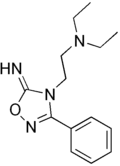

Imolamine (INN, BAN; brand names Angolon, Angoril, Circuline, Irri-Cor, Irrigor, Coremax) is a coronary vasodilator which is used in the treatment of angina pectoris and as a local anesthetic.[1][2]

The reaction of benzoylchloride oxime [698-16-8] (2) with Cyanamide (3) gives 3-Phenyl-1,2,4-oxadiazol-5-amine [3663-37-4] (4). Alkylation with 2-chlorotriethylamine [100-35-6] (5) in the presence of KOH base occurs at the endocyclic ring nitrogen completing the synthesis of imolamine (6).